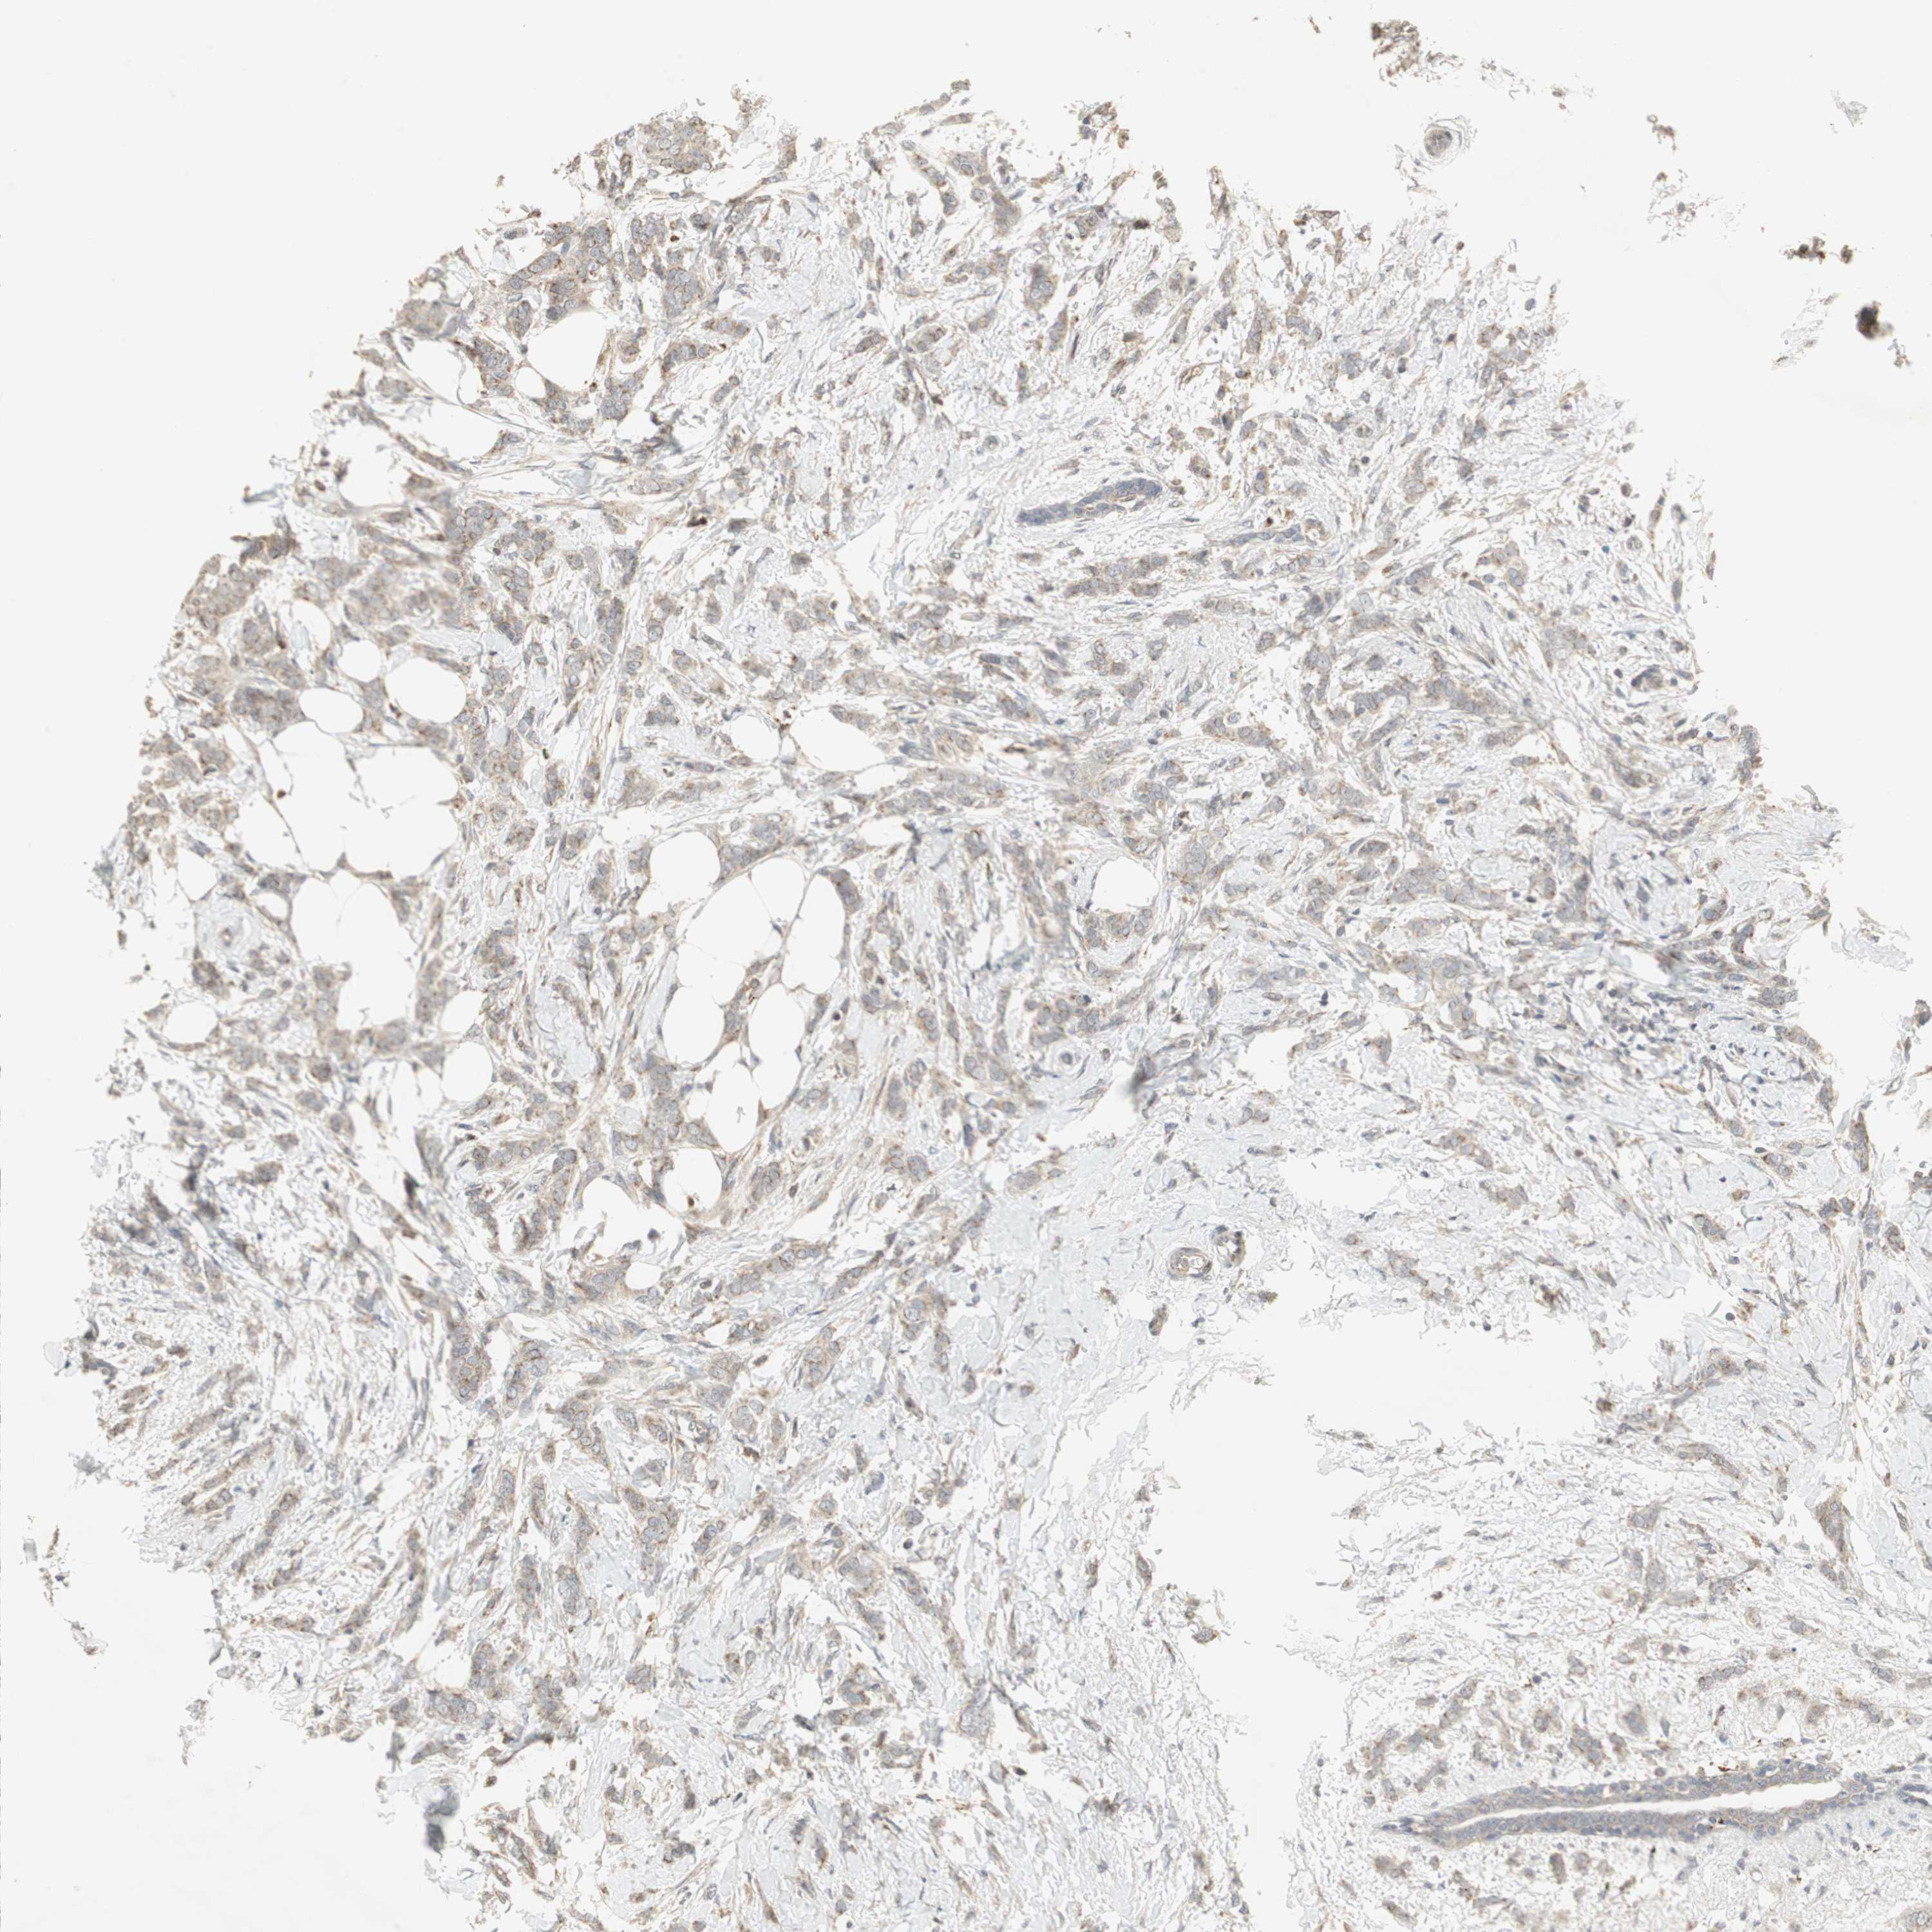

CANCER BREAST CANCER Show tissue menu

BRCA TCGA BRCA VALIDATION PROTEIN EXPRESSION

Breast cancer

Human cancer

SNX4 is not prognostic in Breast Invasive Carcinoma (TCGA)